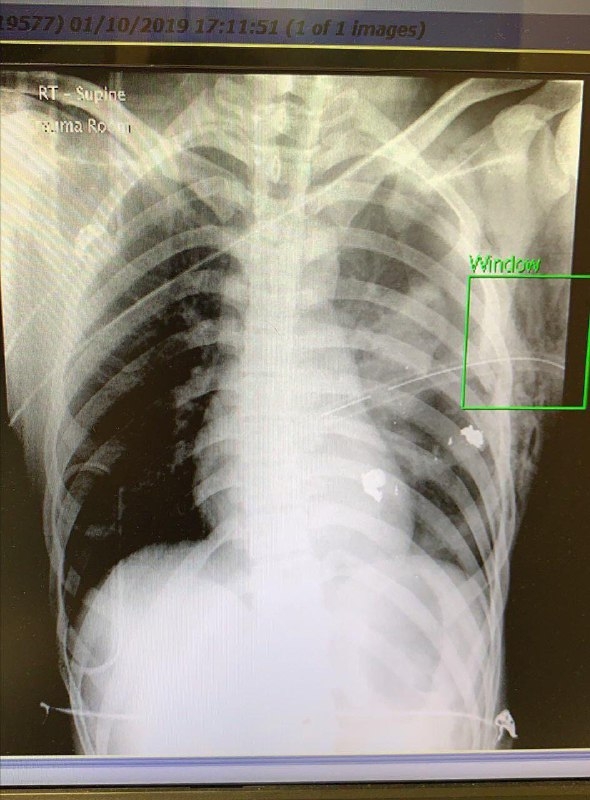

【20:11】據悉,中彈危殆男生已被轉送伊利沙伯醫院,暫時處於危險期。據了解,子彈停留在傷者胸腔內,需要做手術取出,並進行胸腔引流;傷者肋骨亦有骨折,及有血氣胸,幸主要血管沒受損,心臟及肝臟等主要器官正常

【21:50】據悉,中槍男生已完成手術,被送入深切治療部。有知情醫護形容,初步估計男生「應該捱得過」,萬幸是子彈穿過肺部,在肺部與心臟之間邊緣穿過,沒傷及心臟及大動脈